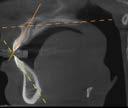

Estudios tomográficos

En el corte sagital ( Figura 8 ) se muestran las inclinaciones dentales alteradas hacia vestibular de ambos incisivos. Finalmente en una vista

axial la forma de arcos cuadrada y la malposición dental clasificada como apiñamiento leve.

Figura 8. Cortes sagital, inclinaciones dentales superior e inferior, axial tomográfico de las arcadas.